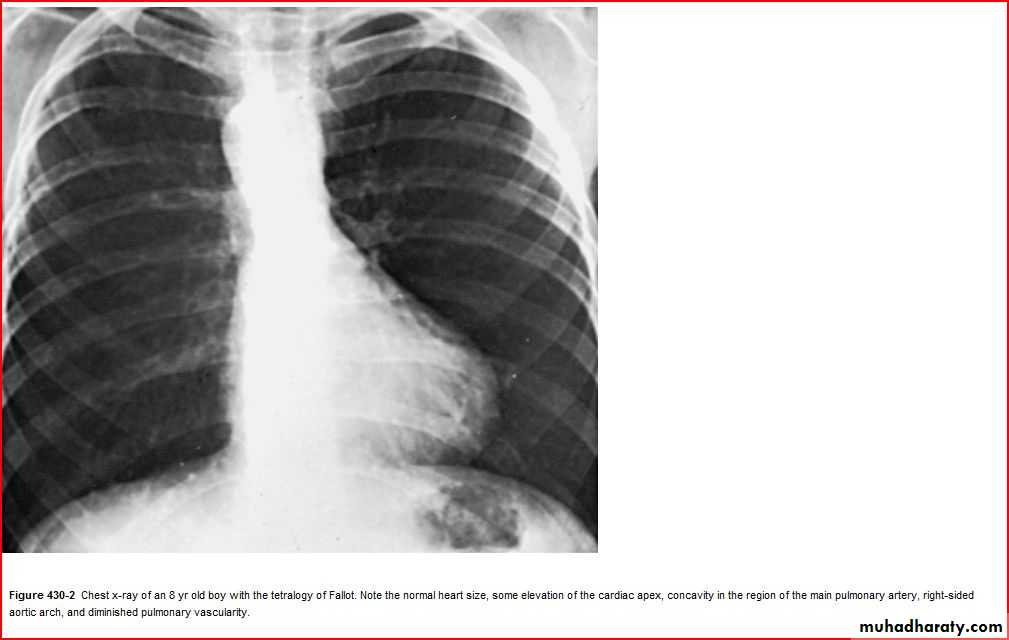

Oligemic lung (devoid vascularty of lung )

Elevation of heart apexRt. Sided aortic notch

BOOT SHAPE HEART ( TOF )